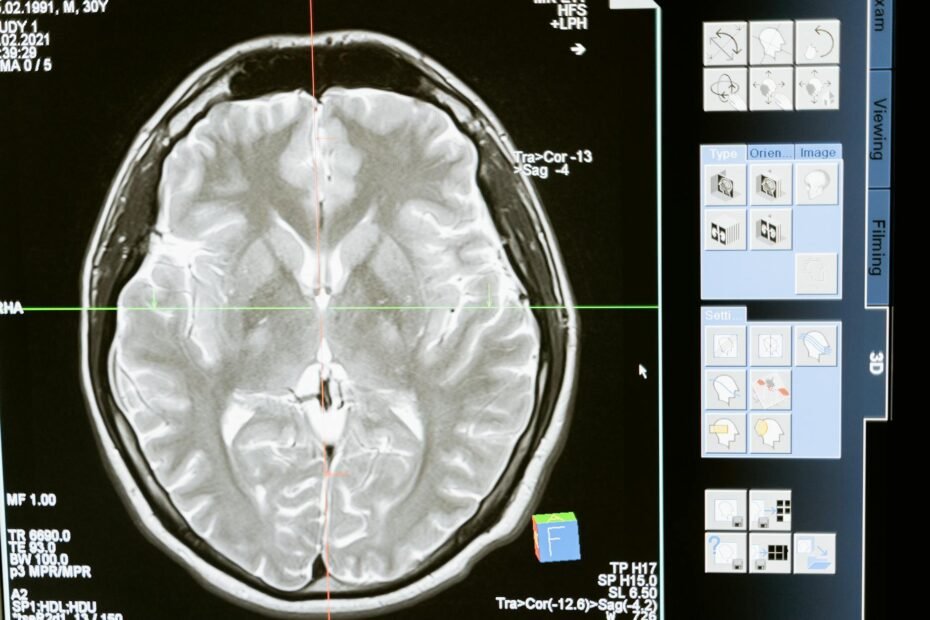

myTomorrows, a global health technology company connecting patients with all possible treatment options, today announced a new partnership with brainstrust, a UK-based charity that helps people living with a brain tumor reach their potential and thrive. Under the new partnership, people with brain tumors will be equipped with the means to bolster their knowledge of relevant treatment options, potentially extending to participation in clinical trials and access to pre-approval drugs. Moreover, the partnership provides a new layer of support to clinicians in their efforts to recruit patients to relevant clinical trials. There are 80,000 people living with a brain tumor in England alone, with a patient receiving a diagnosis every two hours. Brain tumors kill more children and adults under the age of 40 than any other cancer, and incidences and deaths from brain tumors are on the rise. With…